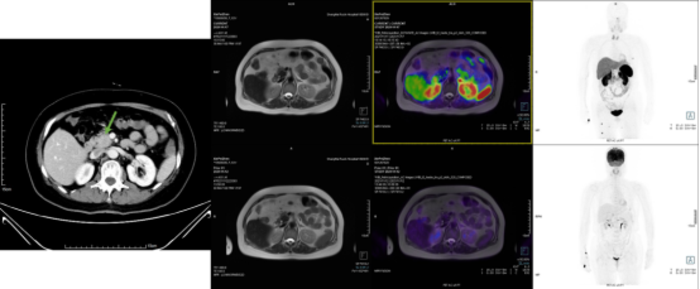

腺泡细胞癌(ACC),是比较少见的胰腺恶性肿瘤,也很容易和神经内分泌肿瘤混淆。好发于中老年人,没有特殊的临床症状,少数可伴有AFP升高,表现为多结节状或分叶状,体积大者中央可以发生囊变坏死,增强后中低度强化、一般低于正常胰腺组织,与周围组织分界较清,此点不同于胰腺导管癌。腺泡细胞癌高度恶性、但预后比胰腺导管上皮腺癌好。病理特点是具有多种结构模式的致密细胞肿瘤,肿瘤细胞巢周围有许多小血管,间质缺乏纤维反应,常见血管侵犯。肿瘤细胞核呈泡状,核仁明显,免疫组化通常Trypsin阳性。腺泡细胞癌通常生长抑素受体显像为阴性。(下图为一例胰头腺泡细胞癌临床资料,本例可见肿瘤代谢不高,肿瘤中心DOTATATE未摄取,边缘局灶摄取增高),该肿瘤很讨厌,能做的就是手术,化疗没什么好的方案。